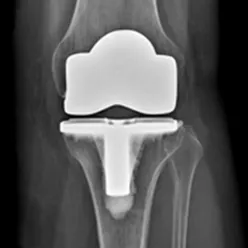

Kneprotesen er ein erstatning for øydelagde leddflater i kneet. Den består av 2 metalldelar som vert festa på lårbeinet og skinnebeinet. Leddflata på lårbeinet består av metall, leddflata på skinnebeinet av høgforedla plast. Metalldelane vert festa med eller utan beinsement. Ei totalprotese dekkjer heile leddflata både på lårbeinet og på skinnebeinet. Det pre- og postoperative forløpet er likt for alle protesetypane.